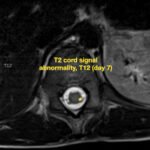

There is a growing body of literature and scientific discovery on pediatric autoimmune encephalitides. This is a heterogenous group of neuroinflammatory conditions leading to often perplexing acute and progressive neurologic and/or neuropsychiatric symptoms. This report demonstrates the evaluation and management of an adolescent with myelin-oligodendrocyte glycoprotein (MOG) antibody-associated fulminant acute disseminated encephalomyelitis (ADEM) in the context of current literature. The featured magnetic resonance imaging uniquely highlights progressive central nervous system lesions detected over the course of the first week of disease.